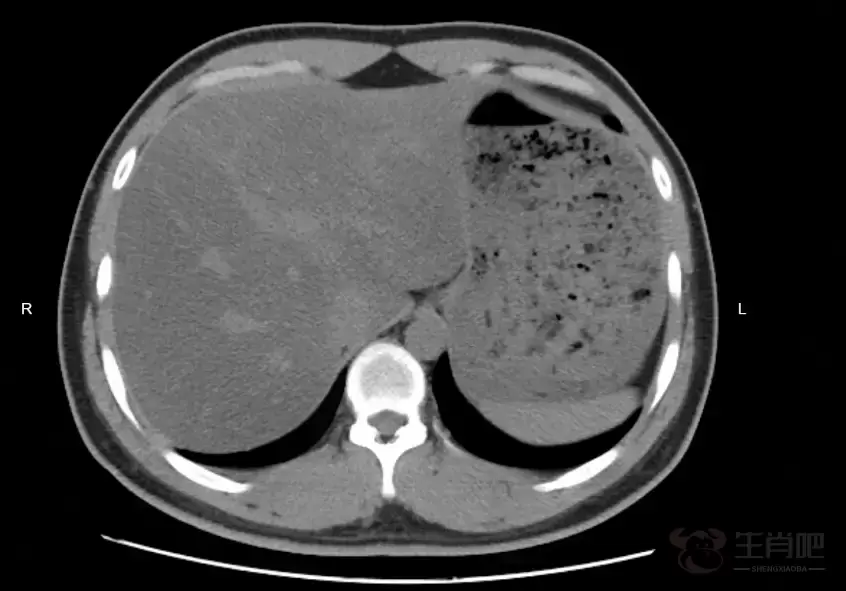

令她始料未及的是,B超检查提示,脂肪肝为中重度。

吃素半年,脂肪肝的程度反而加重了。